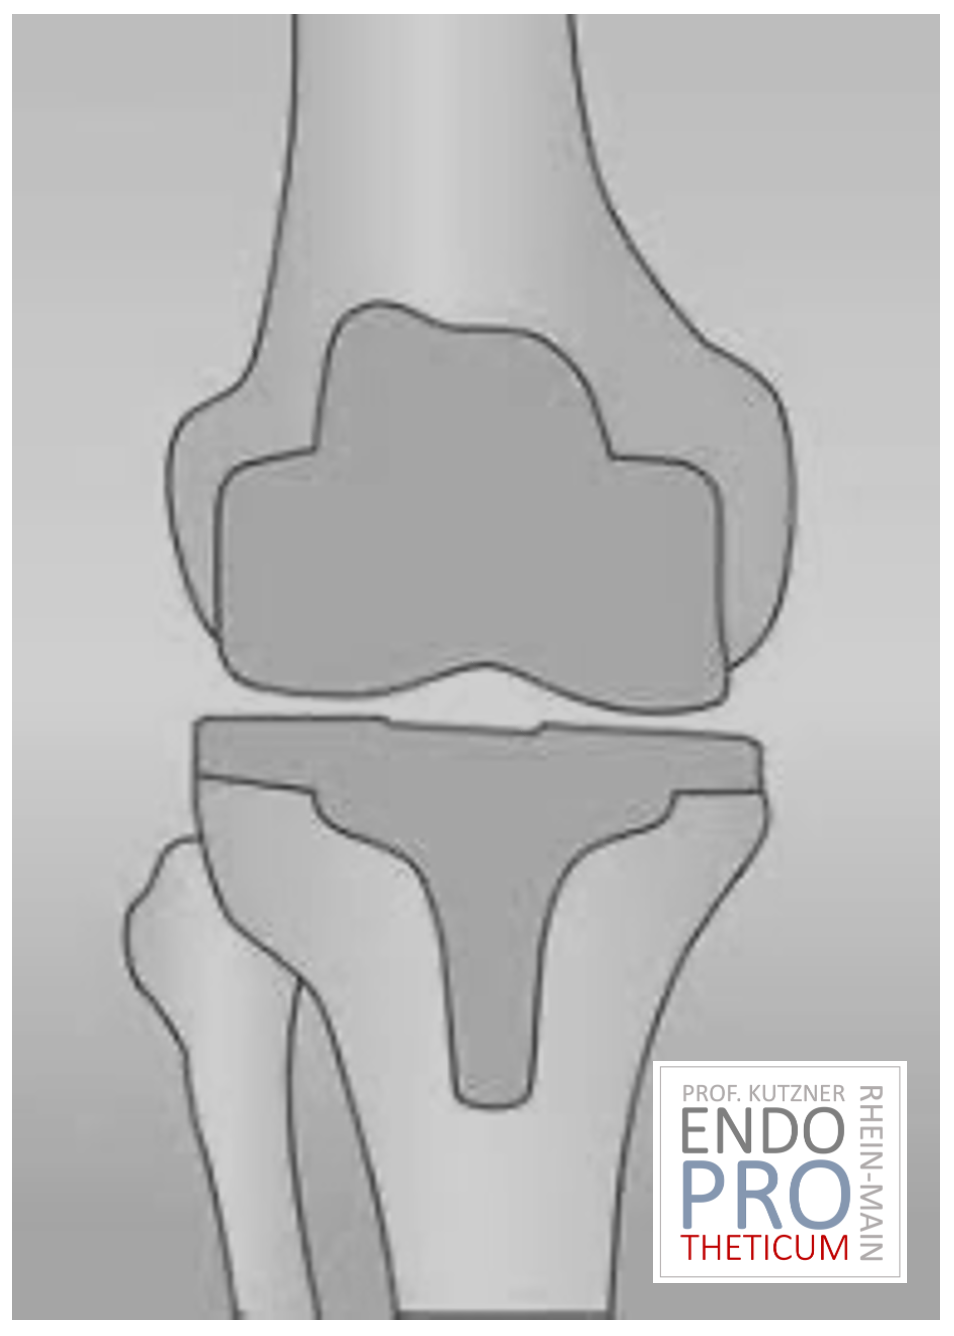

L’articulation artificielle du genou remplace la surface cartilagineuse détruite par l’arthrose. L'os sous-jacent du fémur et de la tête tibiale reste intact. Certains comparent une articulation artificielle moderne du genou à un couronnement de dent ; le terme exact est ce qu'on appelle le resurfaçage bicondylien. Entre les nouvelles surfaces sur la partie supérieure et inférieure de la jambe se trouve ce que l'on appelle une incrustation en plastique blanc spécialement durci, qui peut être vue sur l'image radiographique comme la distance entre les pièces métalliques.

PROTHÈSE DU GENOU À MAÏNZE ET WIESBADEN DANS L'ENDOPROSTHÉTIQUE